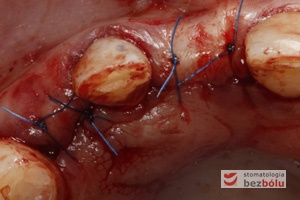

Zamknięcie rany – finisz implantacji – zbliżenie brzegów rany i zaszycie szwami węzełkowymi